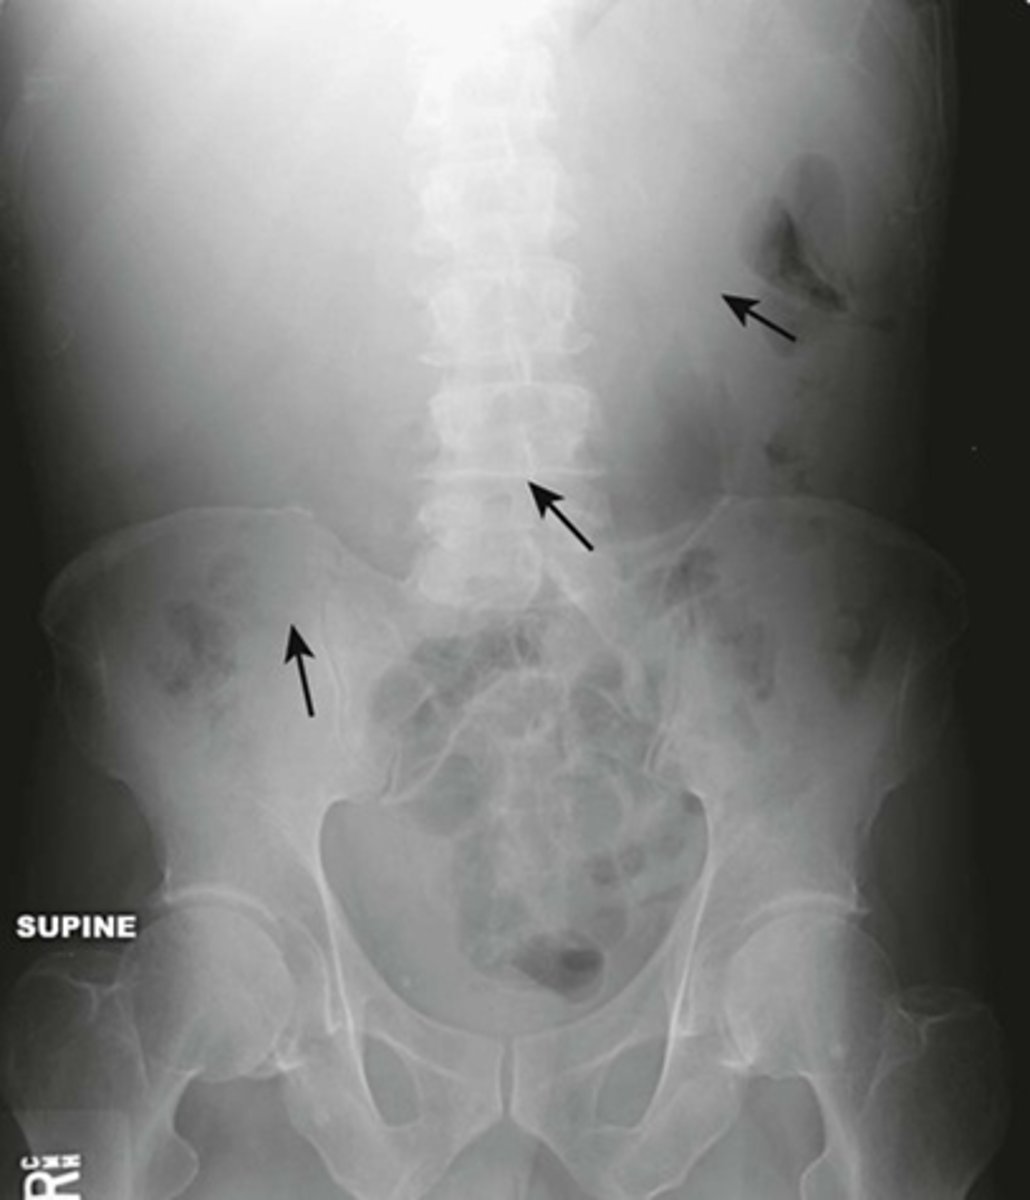

Normal supine abdomen

SOLID BLACK ARROW: small amount of air in about two or three loops of nondilated small bowel

DOTTED BLACK ARROW: air in stomach, always will have.

SOLID WHITE ARROW: air in the rectosigmoid colon.

DOTTED WHITE ARROWS: psoas muscles outlined by fat.